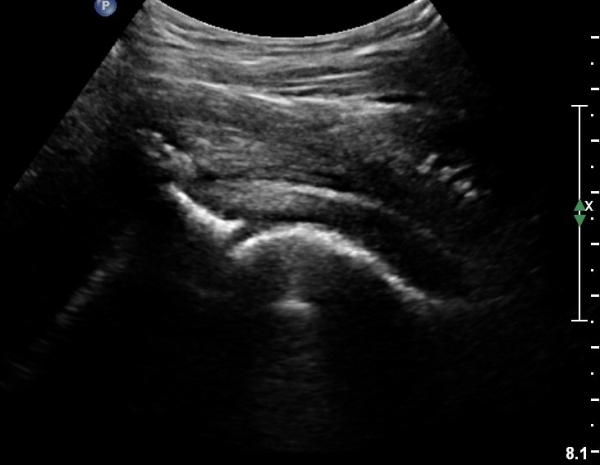

[¾ûµ¢ÀÌ] °í°üÀý Ãæµ¹ÁõÈıº¿¡ÀÇÇÑ È°¾×¸·¿° ÁÖ»çÄ¡·á

ÃÊÀ½ÆÄ °Ë»ç